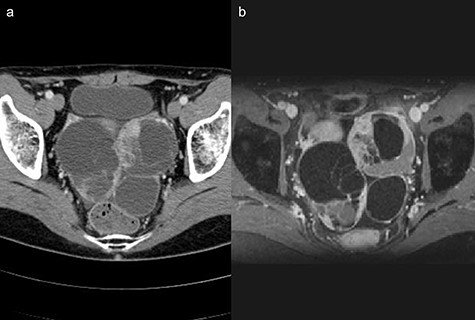

Two years after resection, the patient had no symptoms, but the serum carbohydrate antigen 19-9 became elevated (73 U/mL). CT scan showed a multi-cystic mass in the pelvis with some contrast enhancement (Fig. 6a). Gadolinium-enhanced T2-weighted magnetic resonance imaging revealed a solid mass with contrast enhancement in the cysts (Fig. 6b). Total hysterectomy with bilateral salpingo-oophorectomy was performed. Histological evaluation of the resected specimens showed a proliferation of atypical glandular ducts and expression of CDX2 in glandular tissues, similar to that found in the intestine (Fig. 7a and b). These findings established the diagnosis of a metachronous Krukenberg tumor from adenocarcinoma in a Meckel’s diverticulum. The patient remains free of disease after 1 year of follow-up.

(a) Computed tomography scan showing a multi-cystic mass in the pelvis with a partial contrast effect. (b) Gadolinium-enhanced T2-weighted magnetic resonance image showing a solid mass with contrast effect in the cysts.